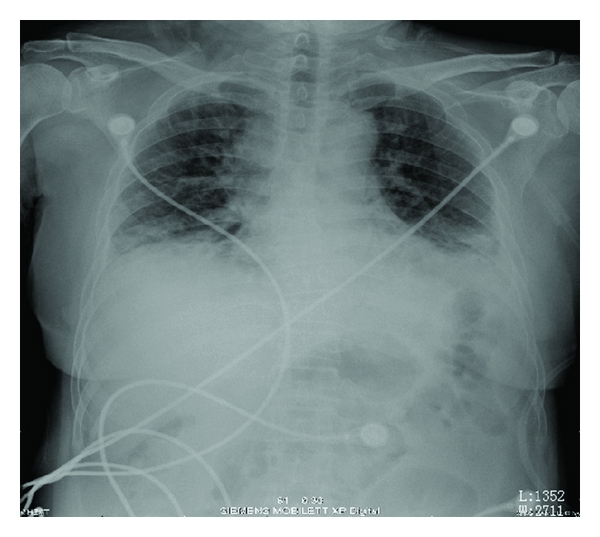

Blood gas analysis revealed Po2 8.54 KPa, Pco2 4.9 KPa, pH 7.421, FiO2/PaO2 = 120. WBCs and HGB were within normal limits. NEU% of 74.1% was slightly increased. Serologic examinations including ANA, Sm, UI-NRnp, Jo-1, Scl-70, SSA, SSB, P-ANCA, RF, C-ANCA, and HIV were all negative. ECG demonstrated sinus tachycardia. Chest radiography was performed which is shown in Figure 1. Her chest CT scan (Figure 2) revealed areas of ground glass attenuation and consolidation in bilateral bases of her lungs accompanied with traction bronchiectasis.

The features of chest radiography from our patient are consistent with typical AIP appearances: progressive, patchy-distributed but not limited to, airspace consolidation and ground-glass attenuation in bilateral lung often diffusely involves the mid and lower zones on X-ray, with the decreased lung volumes. HRCT scan shows bilateral and patchy ground glass attenuation located distinctly at either subpleural or central, leading to a geographic appearance of preserved areas of lung lobules [1, 2]. Consolidation, most common in the dependent area of lung which is seen in the absence of traction bronchiectasis, provides an early radiographic clue to underlying fibrosis [15]. Intralobar linear opacities and subpleural honeycombing may be seen in a minority of cases after the duration of the process continues for more than a month. Later, traction bronchiectasis and architectural distortion which may increase with the duration of the disease [16] are common findings in patients imaged at an organizing stage of disease. Also, cysts and other lucent areas of lung become more common in the late stages of AIP. In reported case, HRCT showed diffused pulmonary infiltration and ground glass attenuation in a geographic appearance, consolidation with associated traction bronchiectasis which confidently fitted into the feature of later phase AIP. The later stage should be another factor to make the pathologic process irreversible even when treated with a steroid pulse therapy.